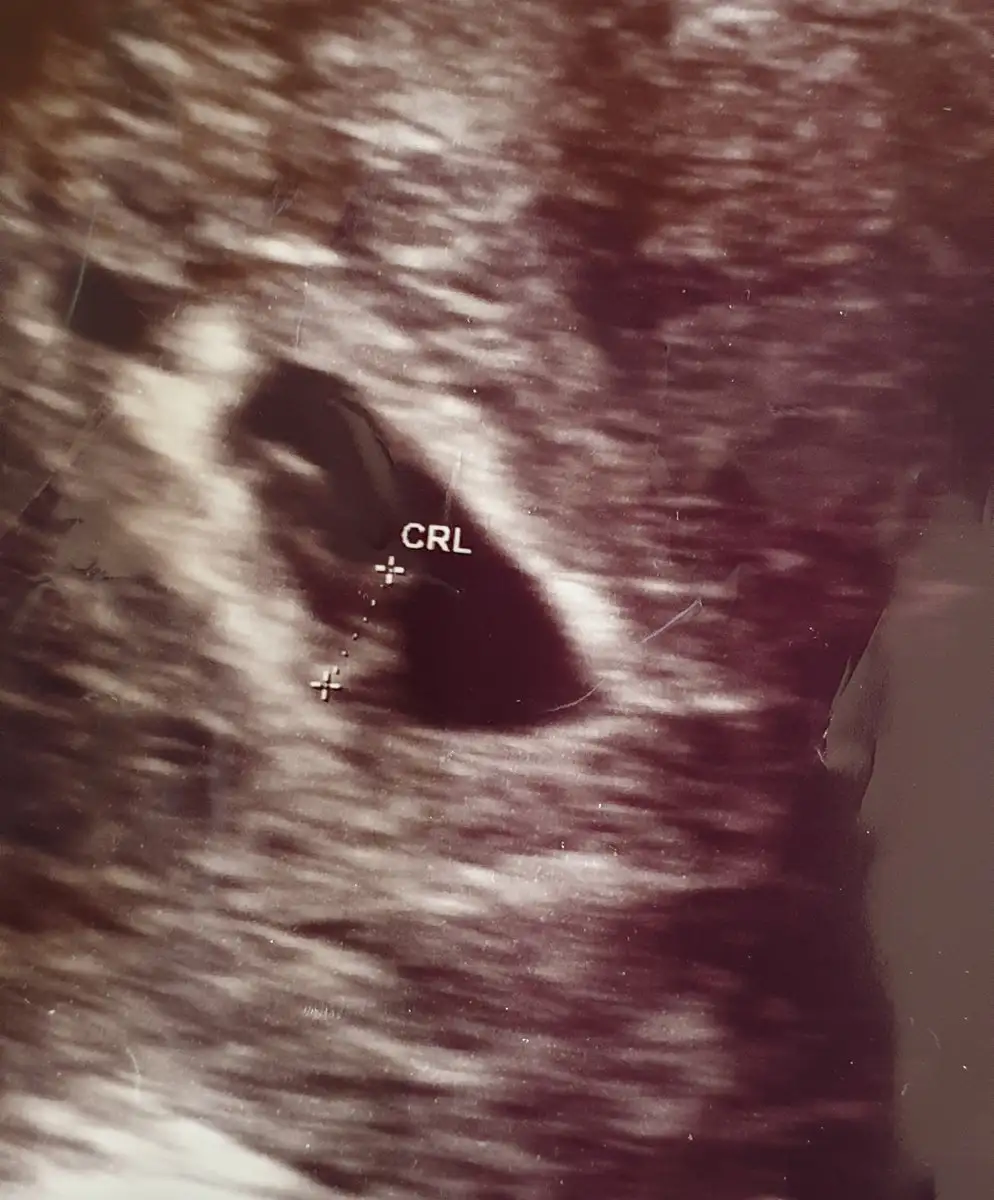

Pikolata banada plesentadan yorum yaparmisin cok rica etsem ilki 7 ikincisi 9 haftalik 2 side karindan usg6 veya 7 haftalık ultrason görüntüsü lazım. bir de karından mı yoksa vajinal mi ultrasonun belirtirsen sana da tahmin de bulunuruz.

Erkek canım

Hala buralardaysan canim banada plasentaya gore yorum yaparmisin 7 hafta ilki digeri 9 Hafta ikiside karindanKız cnm plasentayi net gördüm ama teori bu tabi tutar tutmaz